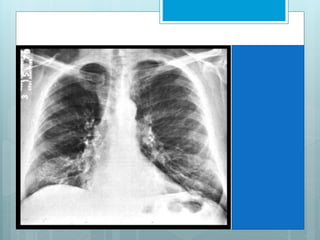

LUL Consolidation

Opacity left hemi-thorax

•Air-bronchogram lines

•Some loss of left heart

border.

Characteristically not a

dense opacity of the PA

view

Opacity Can be sharply

bordered by the oblique

fissure

•Does not involve the

LUL Collapse

 Left major fissure is displaced

ant, roughly parallel to ant

chest wall.

 On PA view it produces a

faint, hazy opacity in left upper

hemithorax, that can be

mistaken for pleural

thickening.

 Left cardiac contour is frequently obscured by lingula.

 Hyper-expanded left lower lobe occupies most of left

hemithorax, with its superior segment occupying apex,

mimicking an aerated upper lobe.

 Left hilar structures are retracted cephalad.